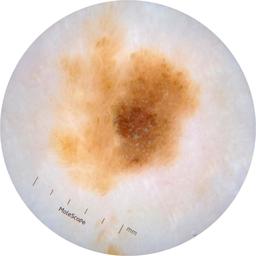

ISIC_6769723

Information

2013 x 2013

Clinical

Field Value

acquisition_day 298

age_approx 45

anatom_site_1 Lower extremity

anatom_site_general lower extremity

concomitant_biopsy False

diagnosis_1 Benign

diagnosis_confirm_type single image expert consensus

family_hx_mm True

fitzpatrick_skin_type I

image_manipulation instrument only

image_type dermoscopic

lesion_id IL_0892257

patient_id IP_5324562

personal_hx_mm True

sex female